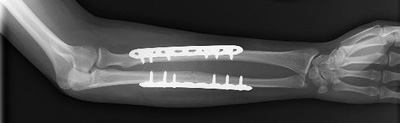

In cases where the skin and other soft tissues around the fracture are badly damaged, an external fixator may be applied until surgery can be tolerated.During this operation, the bone fragments are first repositioned (reduced) in their normal alignment, and then held together with special screws or by attaching metal plates to the outer surface of the bone. The fragments may also be held together by inserting rods down through the marrow space in the center of the bone.

The broken bones of the forearm are held in position by plates and screws while they heal.